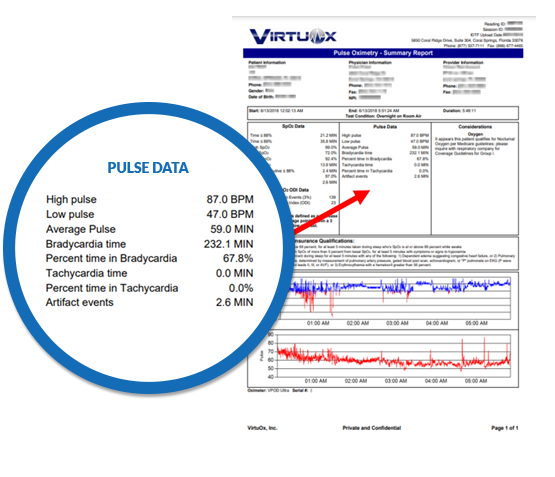

VirtuOx™ offers both a one page summary report and a multiple page detailed report. Both styles are easy to read and include data, as well as graphs.

Did you know?

Hypoxemia can cause serious cardiac arrhythmias

like tachycardia and bradycardia.

With the CardioCHECK enhancement to our

existing overnight pulse oximetry reports,

prescribers can now view the following heart

rate statistics:

- High pulse

- Low pulse

- Average Pulse

- Bradycardia time

- Percent time in Bradycardia

- Tachycardia time

- Percent time in Tachycardia